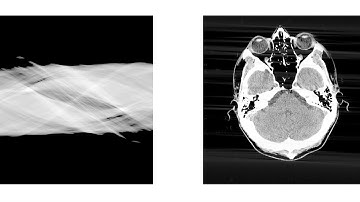

Dynamic Emoji Phantom Tomography with Several Methods